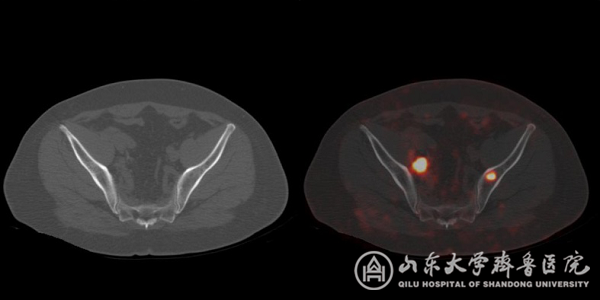

图3 CT未显示骨质破坏而PSMA PET/CT准确显示左侧髂骨骨转移,同时显示盆腔转移淋巴结。